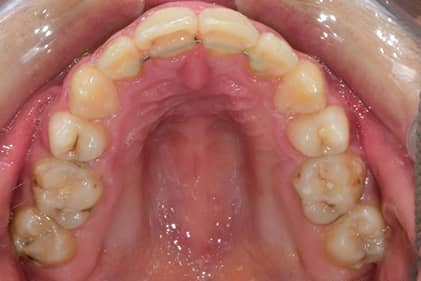

پرونده 1003